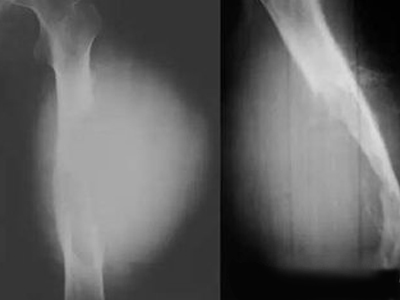

骨膜反应图 (9)

骨膜反应图 (8)

骨膜反应图 (7)

骨膜反应图 (6)

骨膜反应图 (5)